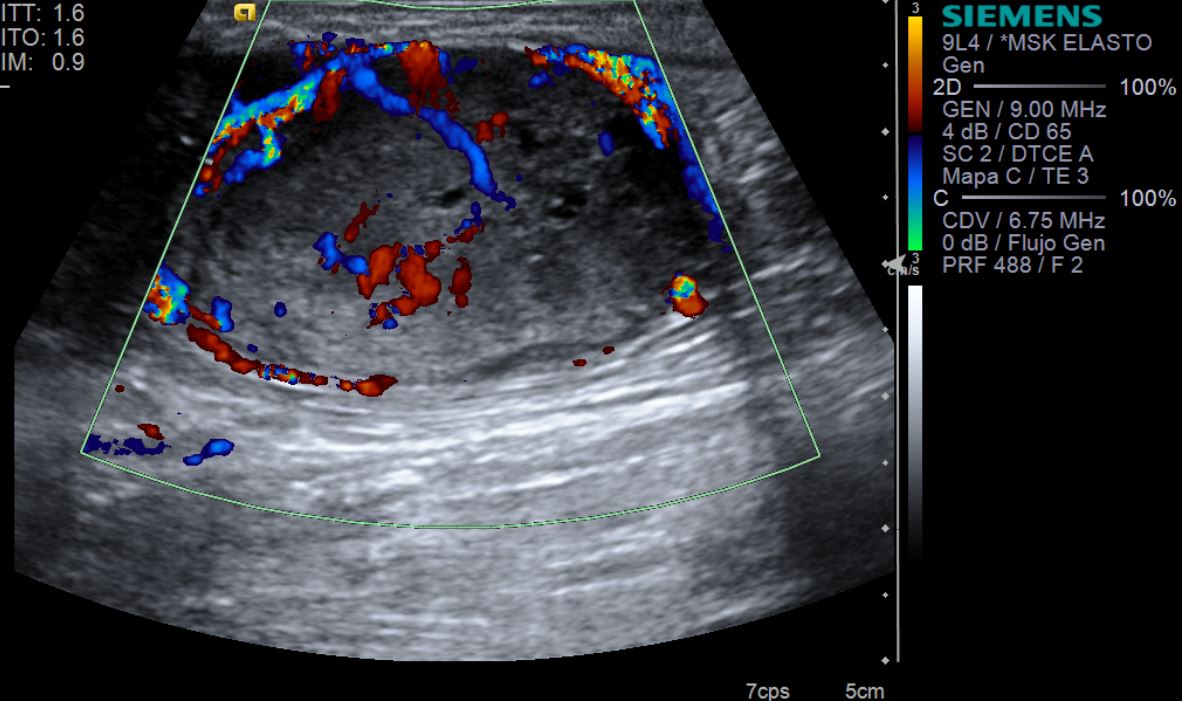

Eco Doppler